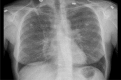

In pulmonary medicine, identical pathogenesis due to varied etiological agents can present with indistinguishable clinical presentation, and produce similar laboratory and radiological changes. The importance of eliciting detailed occupational and social history from patients cannot be stressed enough when dealing with patients suffering from diffuse parenchymal lung diseases. Hot Tub Lung(HTL) is a perplexing pulmonary disease attributed to the Mycobacterium Avium-intracellulare Complex (MAC). MAC is a ubiquitous atypical mycobacterium present in moist environment, and is not considered pathogenic, without the predisposing conditions like immunosuppression. However, HTL is a unique disease seen in healthy individuals following the exposure to contaminated hot water in spas. The less virulent MAC will, in healthy individual will elicit mild granulomatous inflammation particularly around the peribronchiolar region, which leads to the development of diffuse parenchymal lung. We report a case of HTL to increase the awareness of this rare and enigmatic disease among medical professionals, and to reiterate the importance of eliciting social and occupational details in clinical practice.